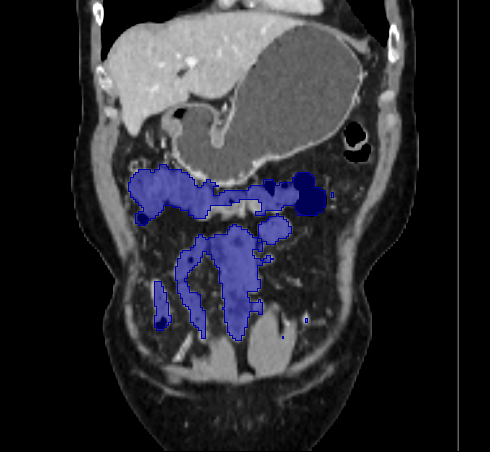

3.2 Qualitative Evaluation

Figure 3 shows example segmentation results in 3D. The result corresponding to ‘feat. & out. level DA’ in Table 1 is compared to ours. We note that the only difference between them is whether the feature disentanglement is involved for the domain adaptation, thus could show its effectiveness. Fewer errors are observed for the proposed method. We believe this is because the proposed method explicitly concentrates on the features more transferable across the datasets, the non-intensity features in this work, by disentangling those features and applying adversarial learning directly to them during the adaptation process. Example reconstruction results from the auto-encoding architecture as well as segmentation results in coronal view can be found in supplementary material.